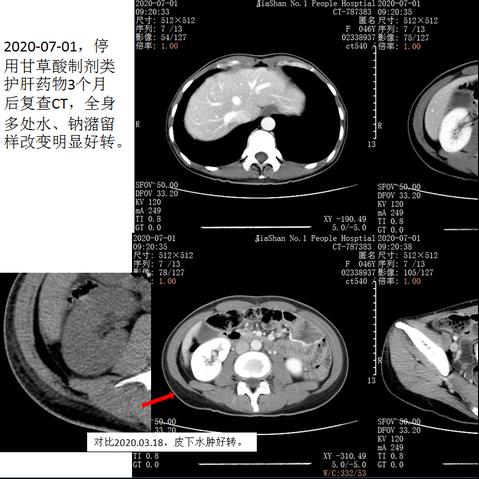

之前就有因为肝功能异常,服用复方甘草酸苷片半月后出现全身浮肿,包括肝周积液、腹腔胸腔等积液等,在排除了低蛋白血症等后,终于锁定元凶并及时更换药物,短期内得到了很好恢复。